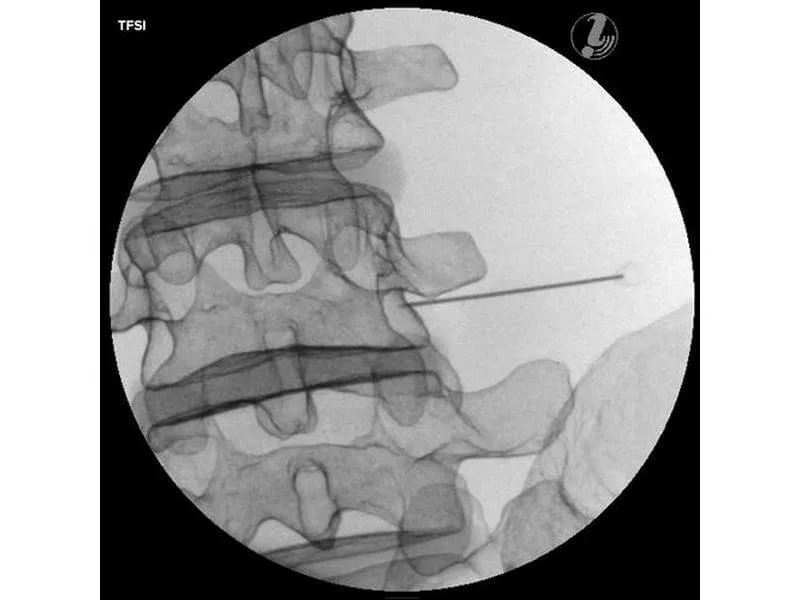

- Трансфораминальная эпидуральная инъекция стероидов (TFSI)